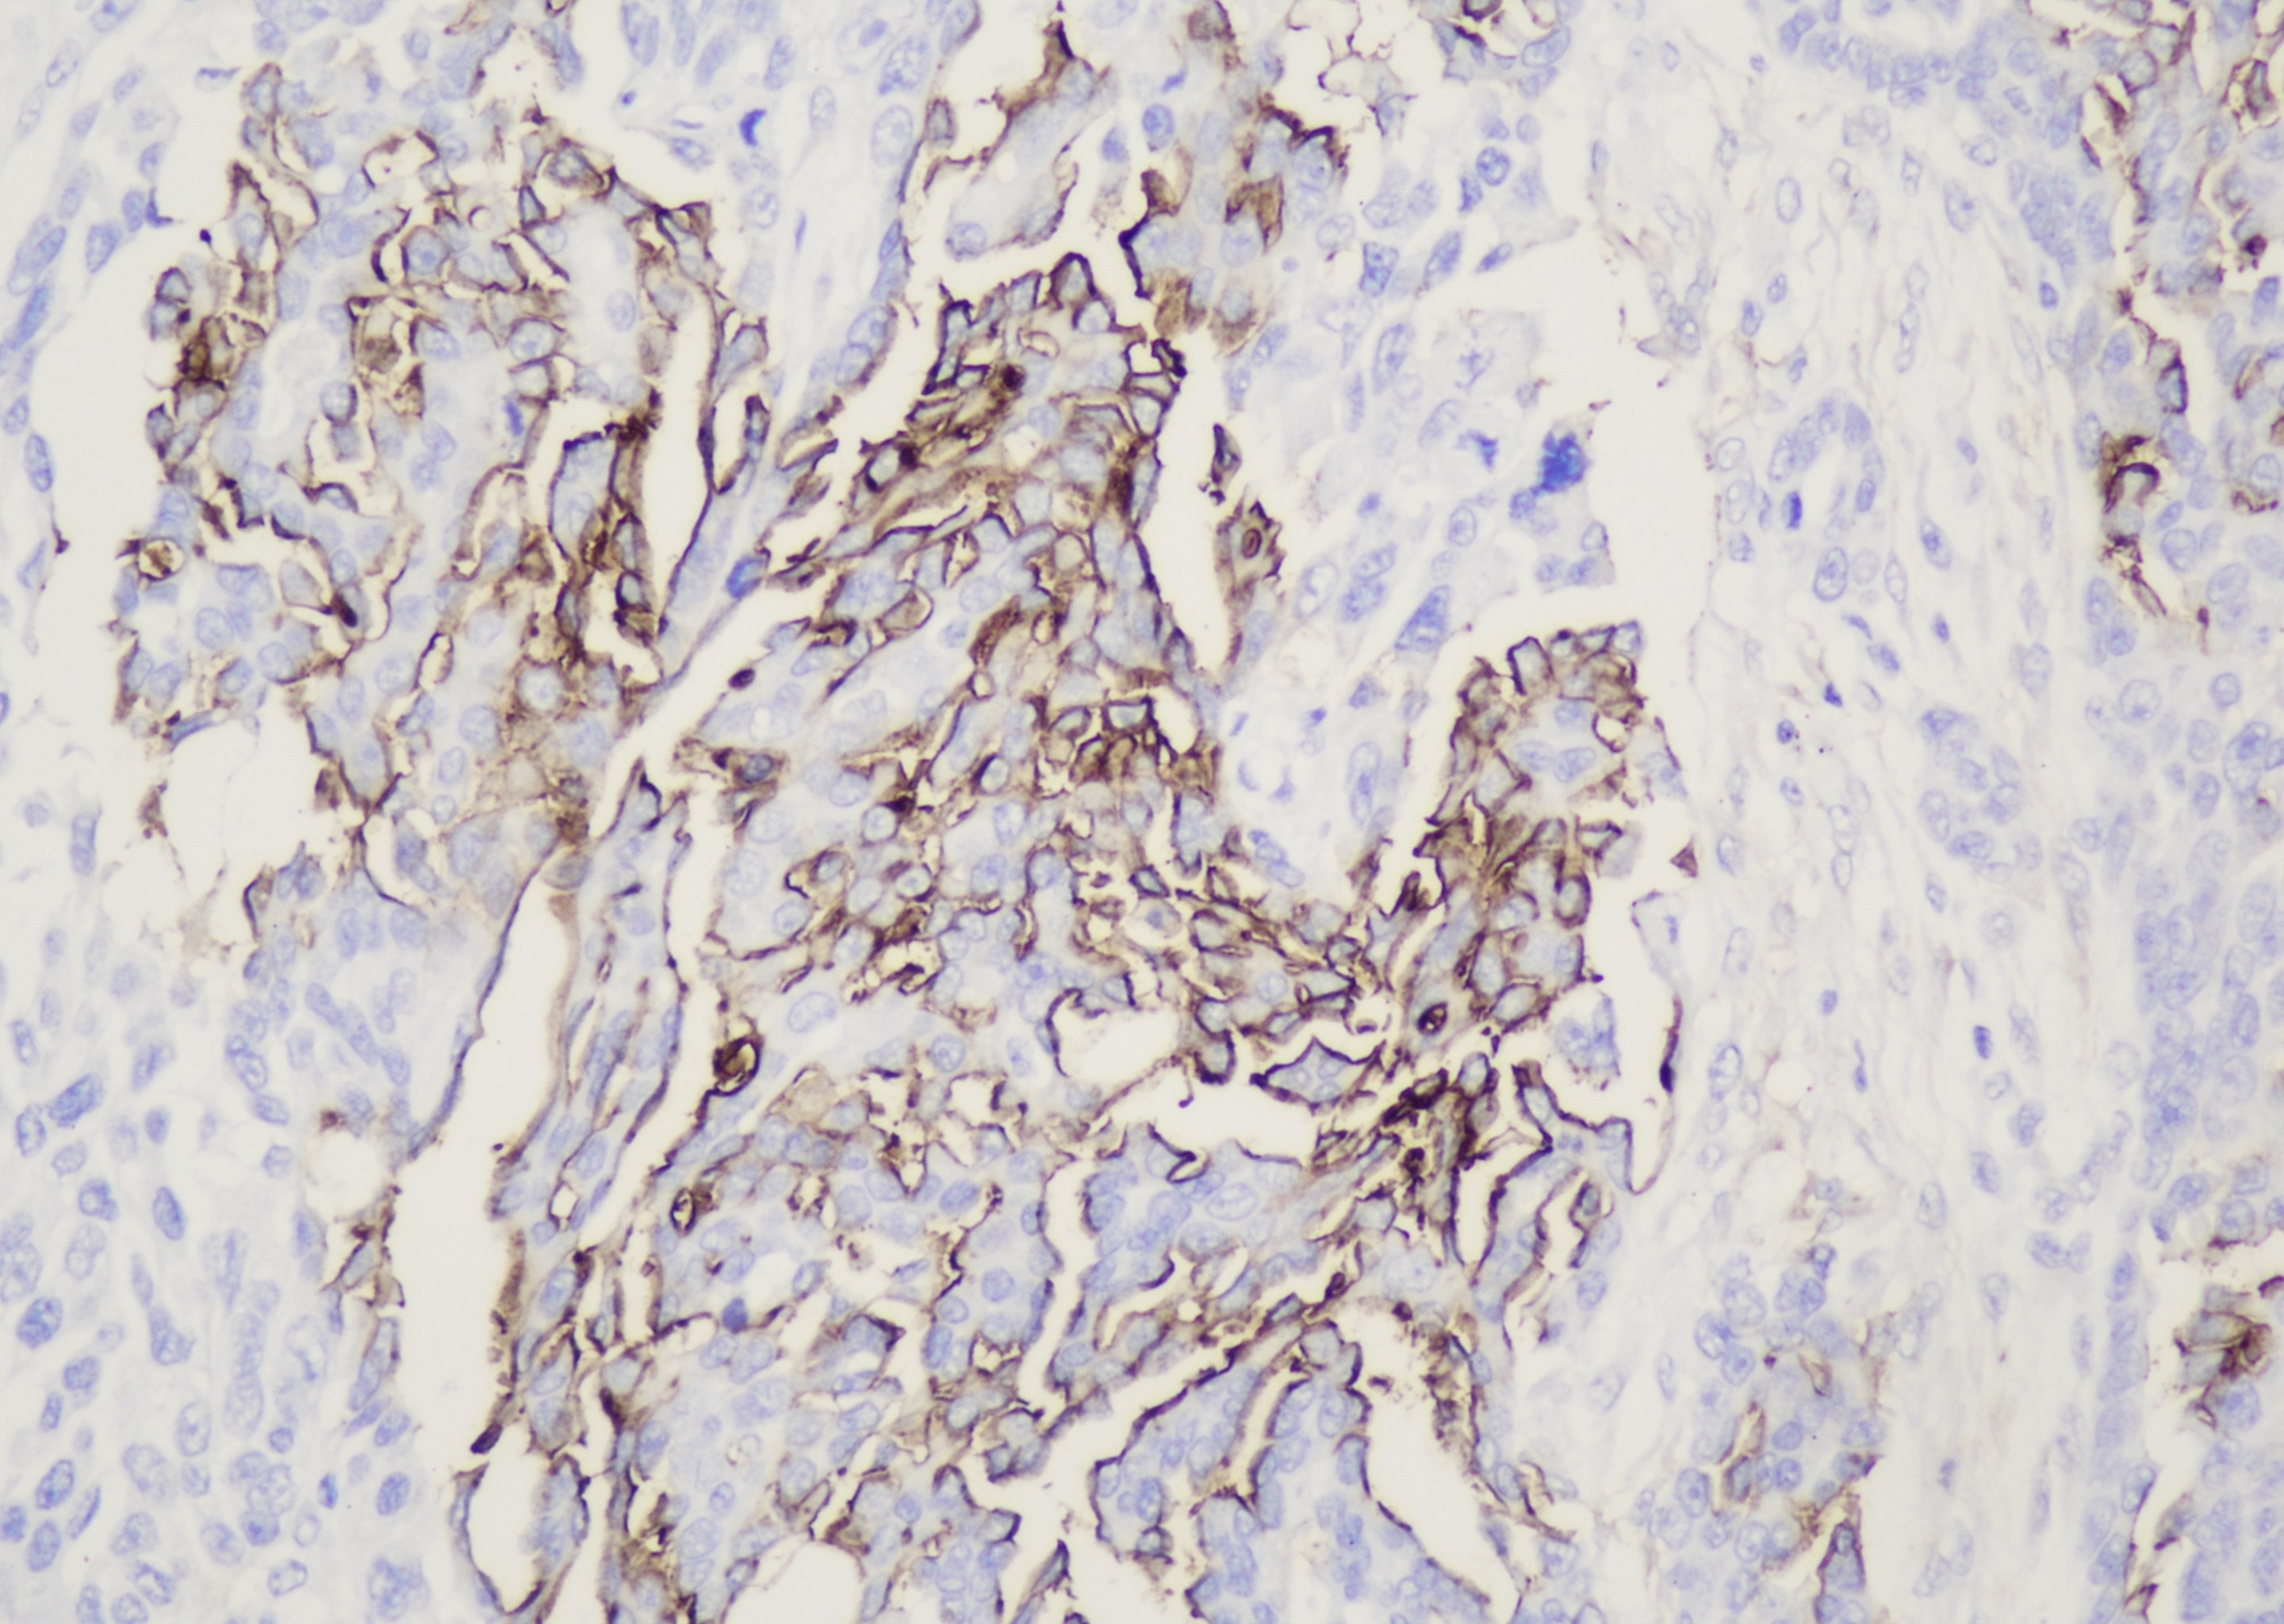

CA 19-9(Carbohydrate antigen 19-9,糖类抗原19-9)是一种肿瘤相关细胞表面糖蛋白,也称消化道癌 抗原,分子量为210kDa。在乳腺、肾、唾液腺、汗腺的导管上皮、肝胆管及导管上皮和前列腺导管上皮中表达。 CA19-9 可用于间皮瘤和腺癌的鉴别诊断、转移性腺癌的鉴别诊断。

| 细胞定位 | 细胞质/膜 |